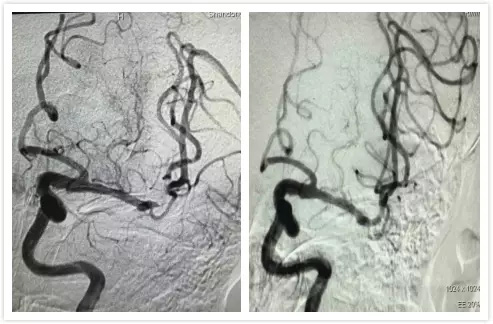

向家属简要知情病情危重性及目前治疗方案的可选项(静脉溶栓已超时间窗,介入动脉取栓可行)。家属表示理解,签署知情同意书后紧急上台行动脉内取栓术。

术中,首先DSA造影再次印证左侧大脑中动脉闭塞,遂行动脉内支架取栓,所取出血栓如下面图片所示。

术后麻醉苏醒后查看患者:患者神志清楚,精神可,查体合作,失语基本恢复,右侧上下肢肌力4级,继续住院治疗1周,出院时患者言语清晰流利,查体合作,右侧肢体肌力基本恢复正常!